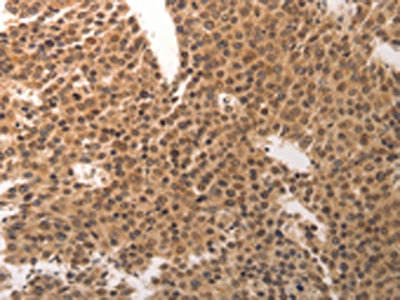

The image on the left is immunohistochemistry of paraffin-embedded Human breast cancer tissue using CSB-PA870444(CDC6 Antibody) at dilution 1/25, on the right is treated with synthetic peptide. (Original magnification: ×200)

The image on the left is immunohistochemistry of paraffin-embedded Human colon cancer tissue using CSB-PA870444(CDC6 Antibody) at dilution 1/25, on the right is treated with synthetic peptide. (Original magnification: ×200)